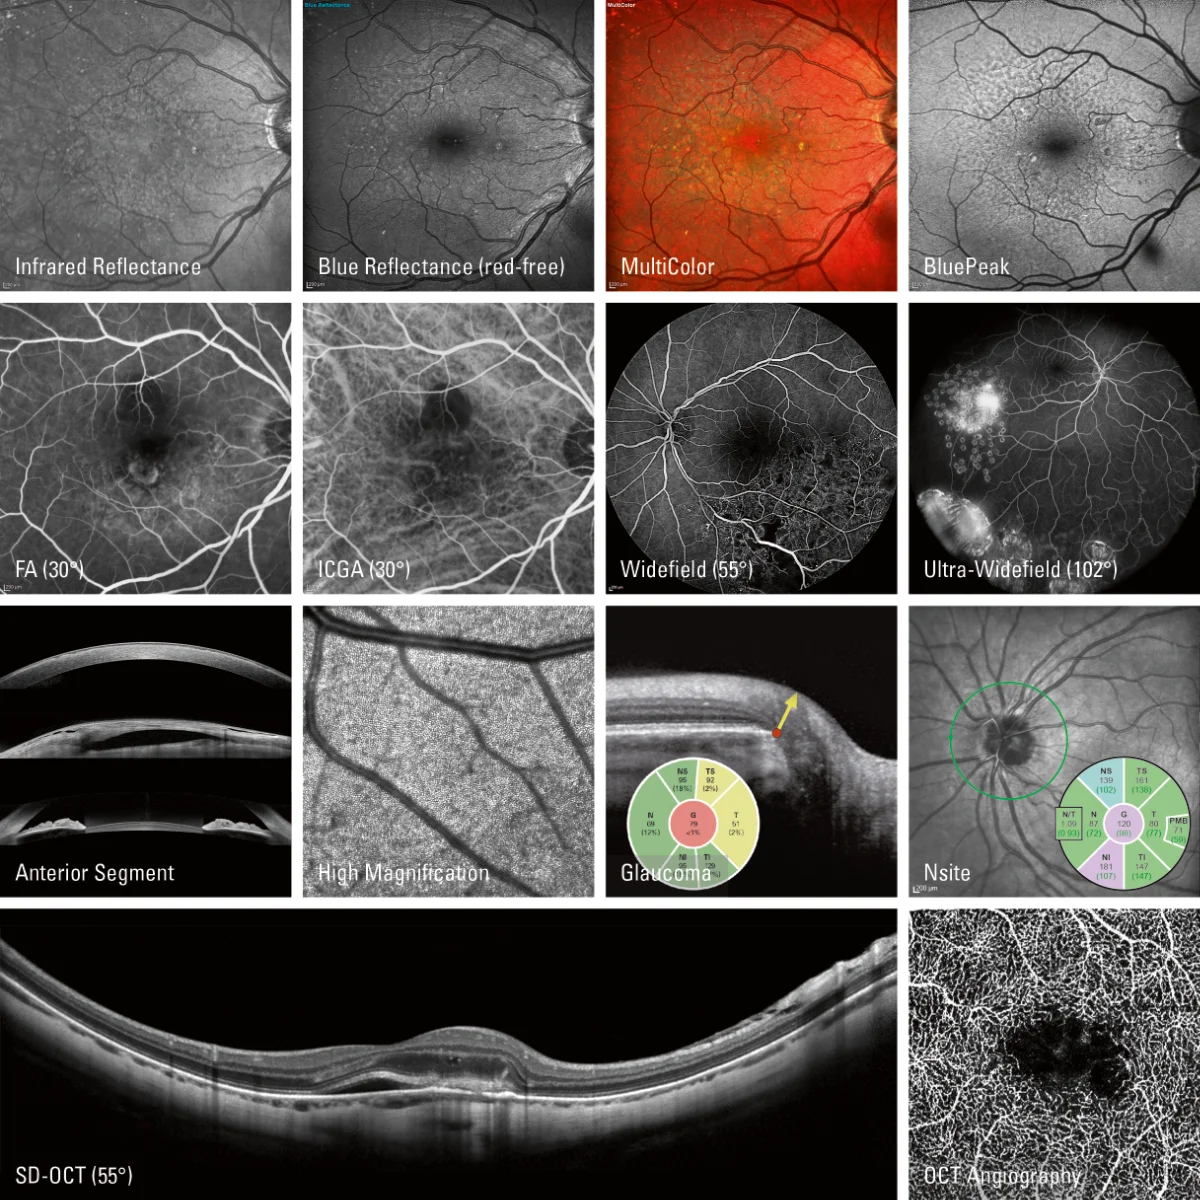

Imaging Multimodale

La combinazione unica delle modalità di imaging di SPECTRALIS® fornisce le informazioni aggiuntive necessarie per prendere decisioni cliniche con maggiore sicurezza. È possibile configurare un sistema di imaging multimodale in base alle proprie esigenze e acquisire diverse tecniche in modo simultaneo, migliorando la comprensione di un’ampia varietà di patologie senza dover spostare i pazienti tra dispositivi e sale d’esame.

Modulo BluePeak — Autofluorescenza Laser Blu

BluePeak è una modalità di imaging del fundus laser a scansione non invasiva che rivela malfunzionamenti metabolici di rilevanza diagnostica in condizioni come la degenerazione maculare legata all’età (AMD).

L’autofluorescenza BluePeak utilizza la lipofuscina come indicatore dello stress metabolico retinico. Combinando la segmentazione OCT con la mappatura metabolica, si rendono visibili le alterazioni morfologiche associate ai cambiamenti funzionali. Con il software RegionFinder, le aree patologiche possono essere quantificate e monitorate nel tempo.

Modulo MultiColor — Imaging Multispettrale del Fundus

MultiColor utilizza tre lunghezze d’onda laser simultanee per catturare un’immagine combinata del fundus, rivelando dettagli retinici non visibili con la fotografia convenzionale. La penetrazione variabile di ciascuna lunghezza d’onda, integrata con l’imaging OCT, fornisce dettagli strutturali che aiutano a localizzare la patologia e a identificare gli strati retinici coinvolti.

Glaucoma Module Premium Edition (GMPE)

Il Glaucoma Module Premium Edition offre un’analisi completa e personalizzata del complesso del nervo ottico e delle cellule ganglionari. Il sistema di posizionamento anatomico proprietario (APS) garantisce che le strutture fini rilevanti nella diagnostica del glaucoma vengano valutate e confrontate ad ogni visita con precisione assoluta.

Modulo di Analisi Nsite — Neurologia Retinica

Il Modulo Nsite è progettato per monitorare i cambiamenti retinici nei pazienti con neuropatie ottiche e processi neurodegenerativi, tra cui sclerosi multipla, morbo di Parkinson, ipertensione intracranica idiopatica e morbo di Alzheimer.

La retina come finestra sul cervello: il Modulo Nsite misura la proiezione neuronale e assonale all’interno della retina, offrendo una prospettiva unica sulla neurodegenerazione.

Angiografia OCT (OCTA)

Il modulo OCTA fornisce immagini ad alta risoluzione del flusso vascolare retinico in modalità non invasiva, con versatilità nel campo visivo, nella velocità di scansione (supportata dalla tecnologia SHIFT) e nella risoluzione dell’immagine.

Combinato con il sistema TruTrack, il modulo OCTA consente la segmentazione di tutti e quattro i plessi vascolari retinici convalidati istologicamente. Lo strumento PAR (Projection Artefact Removal) rimuove automaticamente gli artefatti, migliorando ulteriormente la qualità dell’immagine.

Modulo del Segmento Anteriore

Il Modulo del Segmento Anteriore consente immagini OCT ad alta risoluzione non invasive della cornea, degli angoli della camera anteriore, della sclera e delle strutture circostanti. Ideale per la valutazione dello spessore corneale e dell’angolo della camera anteriore.

Modulo di Imaging a Campo Ampio (Widefield)

Il Widefield Imaging Module offre un campo visivo di 55° per tutte le modalità di imaging del fundus — MultiColor, BluePeak, riflettanza a infrarossi, angiografia e OCT. Catturare macula, testa del nervo ottico e aree periferiche in un’unica immagine semplifica i protocolli diagnostici e facilita il rilevamento delle patologie periferiche.

Modulo di Imaging Ultra-Widefield

Il modulo SPECTRALIS Ultra-Widefield cattura un campo visivo estremamente ampio (102°) in un’unica acquisizione, con immagini uniformemente illuminate ad alto contrasto anche ai margini. Compatibile con angiografia laser a scansione con fluoresceina e ICG, acquisibili singolarmente o in simultanea.

Modulo ad Alto Ingrandimento

Il Modulo ad Alto Ingrandimento consente l’imaging cSLO ad alta risoluzione di microstrutture retiniche precedentemente impercettibili. La lente d’ingrandimento innovativa e il software dedicato dimostrano la capacità del cSLO di risolvere microstrutture oculari riducendo la diffusione della luce intraoculare — rivelando dettagli diagnostici critici non visibili con la fundoscopia tradizionale.

Angiografia a Scansione Laser (FA e ICGA)

L’angiografia laser a scansione è disponibile con fluoresceina (FA) e con colorante verde indocianina (ICG). Entrambe le modalità producono immagini ad alta risoluzione e sequenze video dettagliate del flusso vascolare. Per efficienza clinica e precisione diagnostica, FA e ICGA possono essere acquisiti simultaneamente e in combinazione con l’imaging OCT.